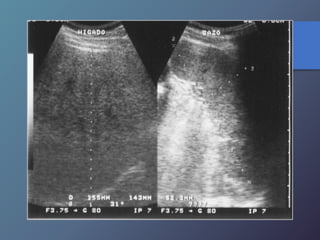

Metástasis • Su incidenciadepende del tipo de tumor. • Localizaciones mas frecuentes del TU primario: vesícula biliar, colon, estomago, páncreas, mama y pulmón. • Pueden presentar una sola lesión hepática, aunque suelen tener múltiples masas focales. Mt Hiperecoicas

• Ecográficamente sepresentan las lesiones de tamaño variable con presencia de un halo hipoecoico. • Diferenciar lesiones malignas de benignas por presencia de halo hipoecoico. • Se describen como lesiones ecógenas, hipoecoicas, en diana, calcificadas, quísticas y difusas.

Clasificación de lasMetástasis MT ecogenas: • origen digestivo o chc. MT hipoecoicas: • Son hipovasculares. • Origen CA de mamas, pulmón, páncreas y esófago. • Los linfomas hepáticos pueden manifestarse en masas hipoecoicas, o difusas difíciles de diferenciar por ecografía o TC. MT en diana: • Presentan una zona hipoecoica periférica, con centro hiperecoico. • Frecuente en carcinomas broncogenos.